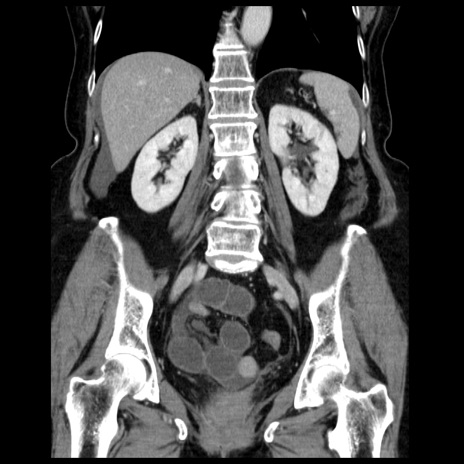

症例13(冠状断像)

【症例】70歳代女性

【主訴】腹痛、嘔吐

【現病歴】15時間程前(昨晩)より腹痛あり。今朝になっても症状の改善なく、嘔吐あり。腹痛も増悪あり、救急外来受診。

【既往歴】子宮癌全摘術後

【身体所見】意識清明、BP 121/72mmHg、P 74bpm、SpO2 100%(RA)、腹部:平坦・軟、腸雑音ほぼ聴取せず。下腹部・心窩部・臍左上に圧痛あり。反跳痛なし。

【データ】WBC 10600、CRP 0.15